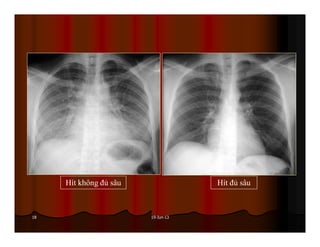

Được xem là hít đủ sâu khi ta thấy được hình chiếu của xương

sườn lên phổi 6 cung sườn trước hoặc 10 cung sườn sau.

Hít không đủ sâu Hít đủ sâu